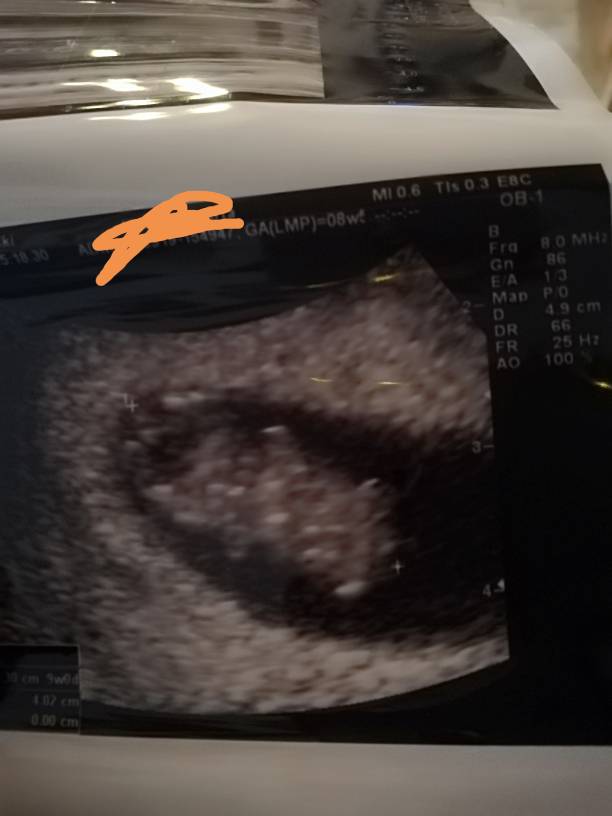

Nasze wizyty i zdjęcia USG :)

Widziałam 2 śliczne maluszki. Oba serduszka pięknie biją. Wszystko idzie w dobrym kierunku.

• 1569319009585.jpeg

1569319009585.jpeg

81,9 KB · Wyświetleń: 307